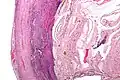

Even for clinically certain appendicitis, routine histopathology examination of appendectomy specimens is of value for identifying unsuspected pathologies requiring further postoperative management.[75] No sign of appendicitis in specimens, negative appendectomy, varies but has been estimated to occur in 13% of specimens.[76] Notably, appendix cancer is found incidentally in about 1% of appendectomy specimens.[77][78]

Pathology diagnosis of appendicitis can be made by detecting a neutrophilic infiltrate of the muscularis propria.

Periappendicitis (inflammation of tissues around the appendix) is often found in conjunction with other abdominal pathology.[79]

Classification of acute appendicitis based on gross pathology and light microscopy characteristics[80]

Pattern Gross pathology Light microscopy Image Clinical significance